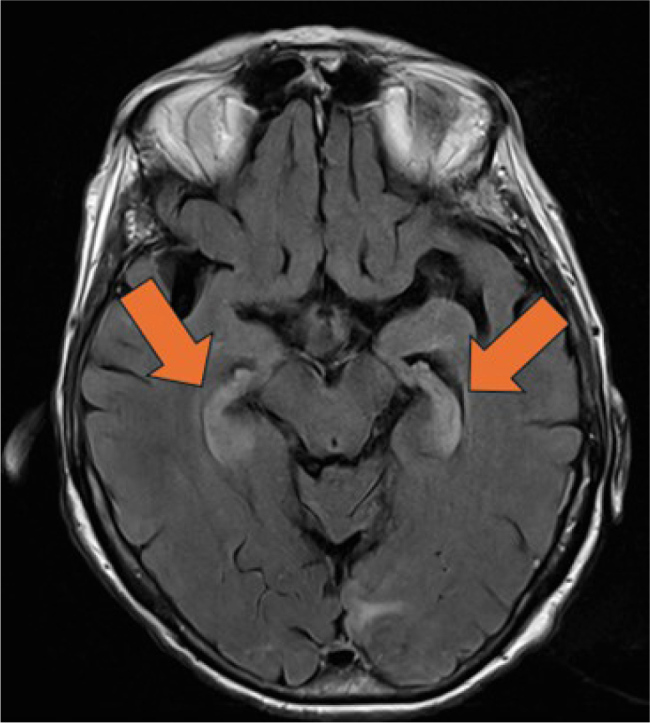

脑炎是一种具有传染性或自身免疫性的潜在威胁生命的疾病。自身免疫性脑炎包括与特异性肿瘤神经抗体(如抗- hu)相关的副肿瘤变异,通常与恶性肿瘤有关。1型单纯疱疹病毒(HSV-1)是导致成人感染的主要原因。区分这些病因是很有挑战性的。我们报告的情况下,一个88岁的妇女入院与混乱后跌倒。初步评估显示临床症状符合脑炎。在住院期间,目睹了癫痫发作。脑脊液(CSF)分析显示轻度多细胞症,但未检测到感染因子,脑成像未显示明显异常。在抗癫痫治疗的初步改善后,患者的认知功能障碍恶化。首次症状出现4周后再次进行脑脊液检查,结果显示细胞增多症更轻,但HSV-1阳性,磁共振成像显示双侧海马高信号。首次脑脊液样本回顾性分析显示高滴度抗hu抗体。正电子发射断层扫描-计算机断层扫描发现高代谢肺病变和主动脉旁淋巴结,活检证实小细胞肺癌的诊断。免疫抑制和肿瘤治疗导致短暂的改善,随后是进行性神经退化。支持性护理最终被优先考虑。该病例强调了脑炎的诊断挑战,特别是当自身免疫和感染性特征重叠时,诊断结果具有误导性。在没有典型的单纯疱疹病毒相关特征的情况下,检测到1型单纯疱疹病毒不应延误对脑炎其他病因的调查。副肿瘤脑炎的早期识别是至关重要的,因为神经系统症状可能先于潜在恶性肿瘤的诊断。学习要点:神经抗体,如抗hu抗体,是脑炎的一种未被充分认识的病因,当临床怀疑是自身免疫性脑炎时,应专门进行检测。检测抗hu抗体需要进行全面的恶性检查。脑脊液中单纯疱疹病毒1型聚合酶链反应阳性不能明确证实活动性感染,必须结合患者的临床表现进行解释。

Encephalitis is a potentially life-threatening condition with infectious or autoimmune aetiologies. Autoimmune encephalitis includes paraneoplastic variants associated with specific onconeural antibodies such as anti-Hu, frequently linked to malignancies. Herpes simplex virus type 1 (HSV-1) is the leading infectious cause in adults. Differentiating between these aetiologies can be challenging. We report the case of an 88-year-old woman admitted with confusion following a fall. Initial evaluation showed clinical signs consistent with encephalitis. During hospitalisation, a seizure was witnessed. Cerebrospinal fluid (CSF) analysis revealed mild pleocytosis, but no infectious agent was detected, and brain imaging revealed no significant abnormalities. After initial improvement under antiepileptic therapy, the patient experienced worsening cognitive dysfunction. Repeat CSF testing 4 weeks after initial symptom onset showed even milder pleocytosis but was positive for HSV-1 and magnetic resonance imaging showed bilateral hippocampal hyperintensities. Analysis of the first CSF sample retrospectively revealed high-titer anti-Hu antibodies. Positron emission tomography-computed tomography scan identified a hypermetabolic lung lesion and para-aortic lymph node, with biopsy confirming the diagnosis of small cell lung cancer. Immunosuppressive and oncologic treatment led to transient improvement, followed by progressive neurological deterioration. Supportive care was ultimately prioritized. This case underscores the diagnostic challenges of encephalitis, especially when autoimmune and infectious features overlap, and diagnostic findings are misleading. Detection of HSV-1 should not delay the investigation of alternative causes of encephalitis in the absence of typical HSV-related features. Early recognition of paraneoplastic encephalitis is critical, as neurologic symptoms may precede the diagnosis of underlying malignancy.